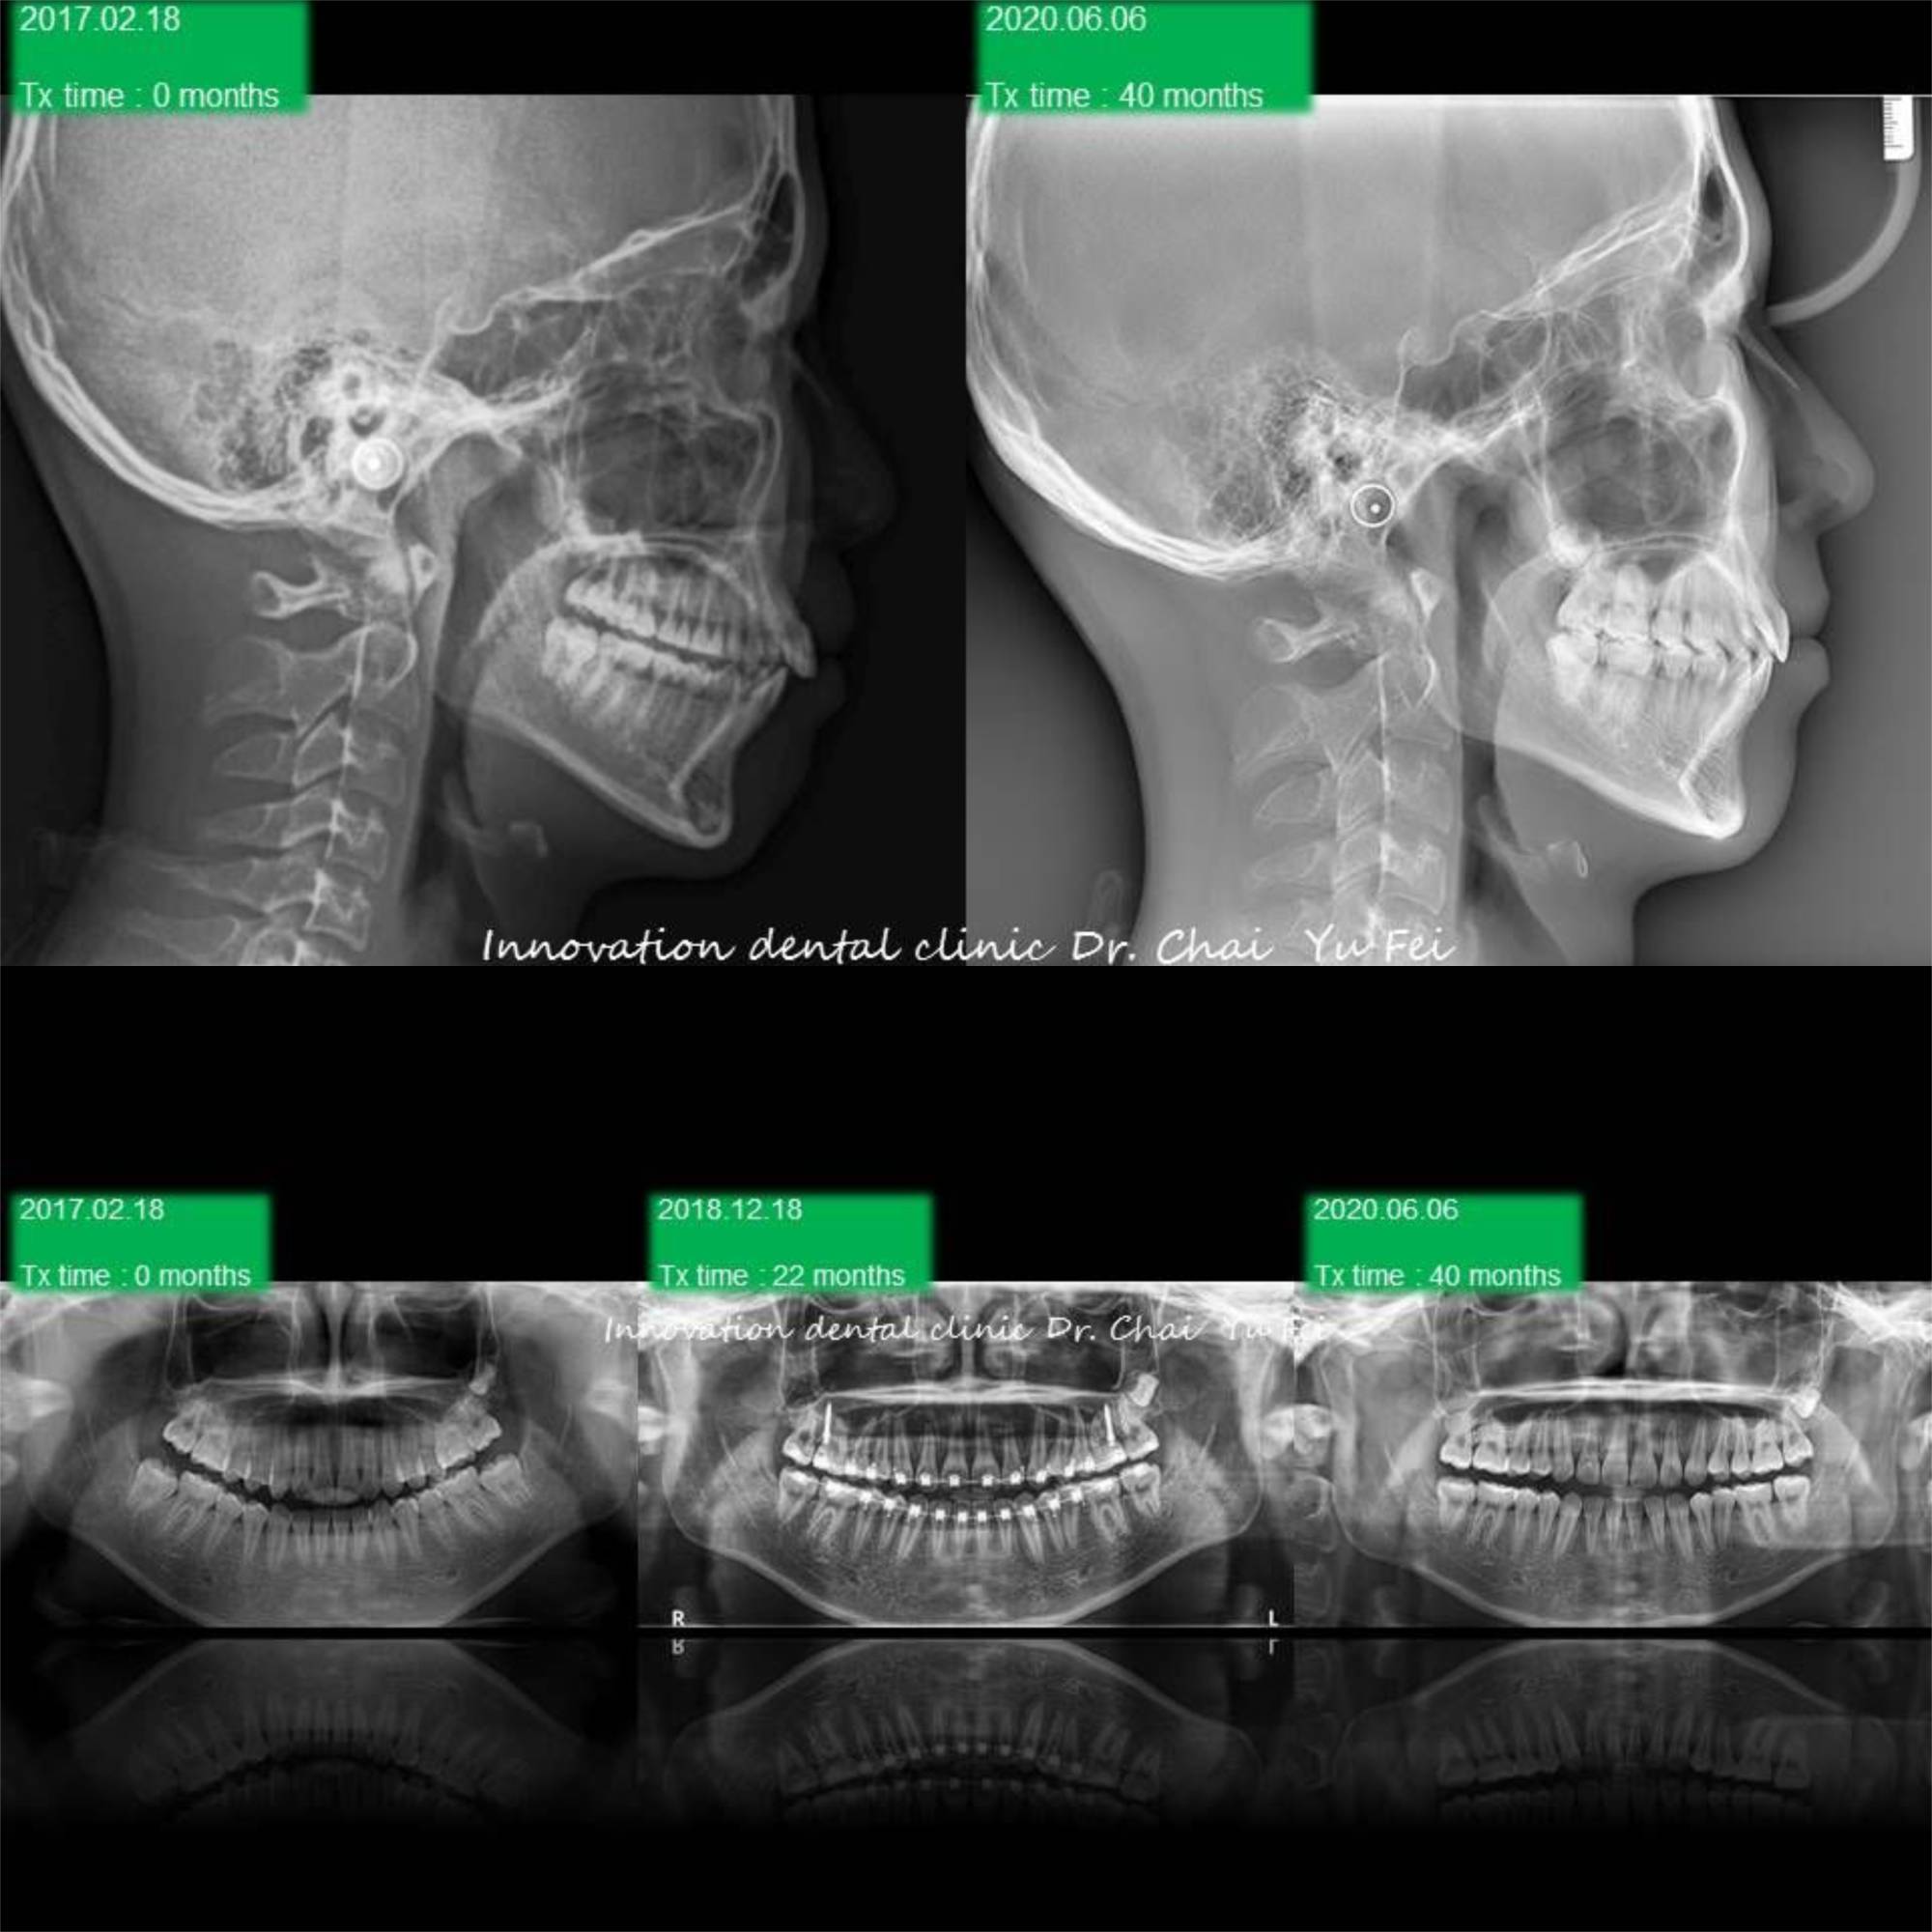

[ 矯正醫師 ] : 展心牙醫 翟聿飛 醫師

[ 治療方式 ] : 利用矯正 , 將前突的齒列內收,改善外觀,右側咬合高度喪失重建,植牙,恢復美觀功能

[ 治療時間 ] : 40 個月

[ 矯正器種類 ] : MBT 18X25 金屬矯正器

男生的發育都是很長遠的,看到初始這樣的暴牙可能會擔心需要拔牙改善,但是考量孩子的年紀與生長潛力

我們採用上顎到後期用骨釘加一層保險去控制,下顎讓孩子自然生長的方式,現在這位高材生都已經升大學了

Non-extraction case .

Upper control by mini screw , lower let him grow automatically